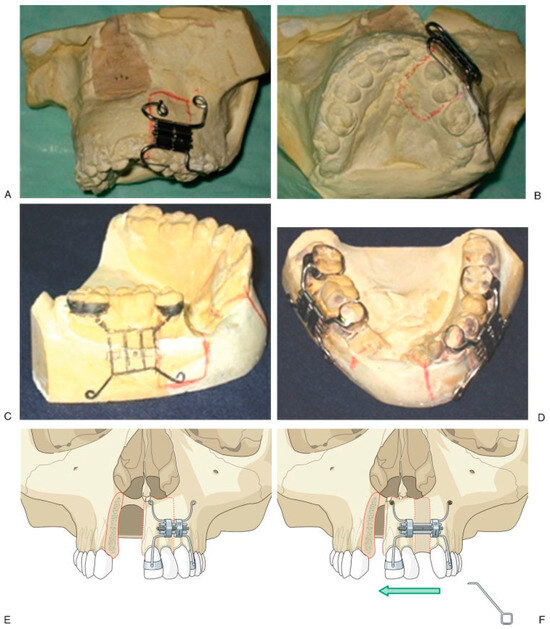

Figure 3. Initial aspect (A–E). Design of the device (F). End bifocal alveolar bone transportation technique (G). Closing of alveolar fistula at 57 weeks of follow-up (H–J). Regenerated new bone behind of the used transport disk (K). - Case 2 was a 16-year-old female patient with sequel of cleft lip and palate and active oronasal fistula, treated with bifocal ABT (Figure 4).

Figure 4. Initial aspect (A–D). There is no anchoring of dental bands, but orthodontic tubes (E). End trifocal alveolar bone transportation technique (F). Aspect at 90 weeks of follow-up (G,H), and radiographics with evidence of closure fissure and osseointegrated implant in the regenerated new bone (I–K). - Case 3 was a 19-year-old male patient with sequel of cleft lip and palate and active oronasal fistula, treated with bifocal ABT (Figure 5).